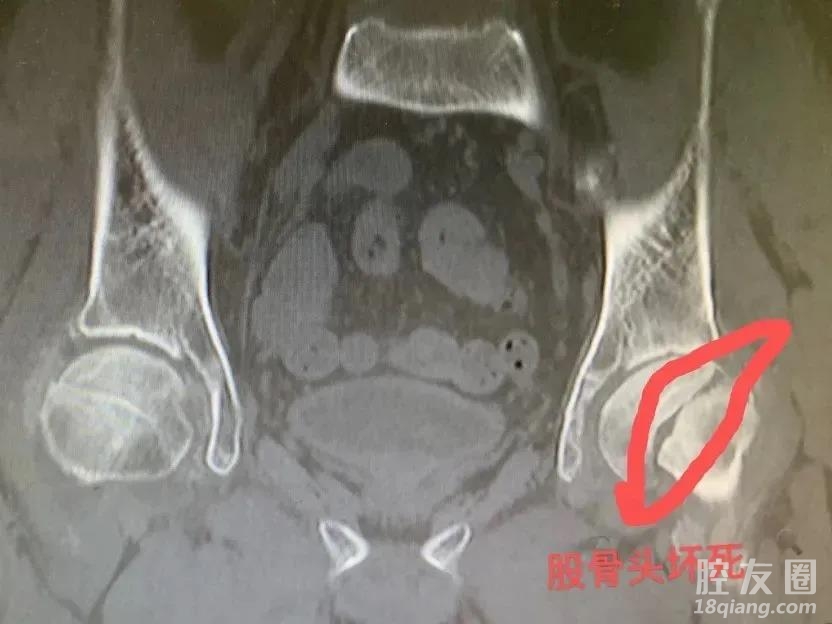

金永鑫介绍,每年医院都会收治一些乱服药、服“乱”药,导致急性肝损伤、肾损伤、药物中毒、股骨头坏死等的患者。其中,有的患者是不遵医嘱错误服药,有的患者是相信偏方自行购药或在网上乱购药,还有的患者是随意购买多种药物,引起了药物交叉反应……结果都导致了严重的后果。“服药、用药一定要遵正规医院医生的医嘱,切莫自行服药及配药。如有使用医嘱外药物也请提前告知医生,避免引起药物交叉反应。”